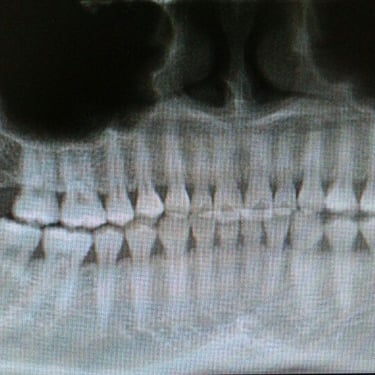

Dientes impactados

Los dientes impactados son dientes que no pueden erupcionar correctamente debido a la falta de espacio o a una obstrucción.

Los pacientes pueden notar que un diente no ha salido, aunque debería haberlo hecho. Esta condición es común con las muelas del juicio y los caninos superiores.

El tratamiento puede incluir la extracción del diente impactado o la creación de espacio para permitir su erupción.